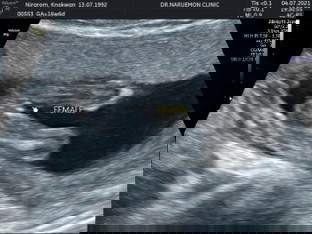

female นี้ขึ้นมาเองใช่ไหมค่ะ ถ้างั้นก็คงผู้หญิงแล้วละคะ

ผู้หญิงจ้าาา